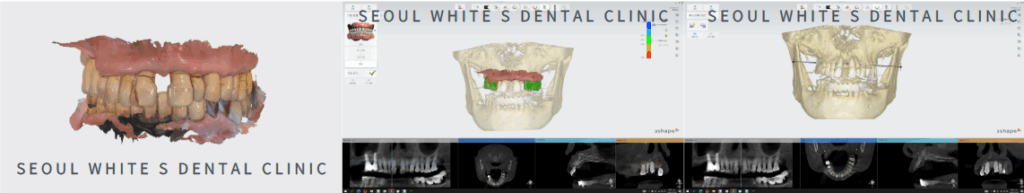

3D CT 촬영과 구강 SCAN을 진행한 자료를 바탕으로 구강상태를 꼼꼼하게 확인하였습니다.

식립할 위치로 모의 시.술을 진행하고, 자체기공소와의 협업을 통해 신속하게 가이드를 제작하였습니다.

식립 후 일상생활의 불편함을 덜어드리기 위해 임시 보철물 제작과 자연스러운 최종 보철물의 형태까지 미리 확인하였습니다.

환.자분께도 진행과정을 보여드리며 안심하고 치료받으실 수 있도록 도와드렸습니다.